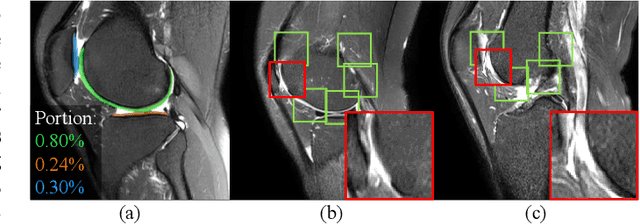

Abstract:Knee osteoarthritis (OA) is one of the most common musculoskeletal disorders and requires early-stage diagnosis. Nowadays, the deep convolutional neural networks have achieved greatly in the computer-aided diagnosis field. However, the construction of the deep learning models usually requires great amounts of annotated data, which is generally high-cost. In this paper, we propose a novel approach for knee OA diagnosis, including severity classification and lesion localization. Particularly, we design a self-ensembling framework, which is composed of a student network and a teacher network with the same structure. The student network learns from both labeled data and unlabeled data and the teacher network averages the student model weights through the training course. A novel attention loss function is developed to obtain accurate attention masks. With dual-consistency checking of the attention in the lesion classification and localization, the two networks can gradually optimize the attention distribution and improve the performance of each other, whereas the training relies on partially labeled data only and follows the semi-supervised manner. Experiments show that the proposed method can significantly improve the self-ensembling performance in both knee OA classification and localization, and also greatly reduce the needs of annotated data.